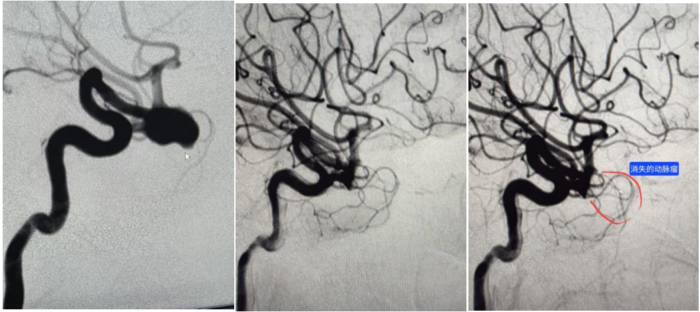

术后复查及对比

经过充分的术前准备,1月13日上午,由许琼冠副主任医师主刀,何少宇、龙丁辉、李佳梦主治医师医师配合,手术在全麻+气管插管下进行。通过右股动脉穿刺,先行全脑血管造影(DSA),在3D影像下精确测量大脑中动脉瘤的大小,并选择合适型号的WEB。在微导丝引导下,将微导管超选置入动脉瘤腔内,成功置入并释放WEB。术毕造影显示,动脉瘤填塞满意,相关血管显影良好,手术取得圆满成功。